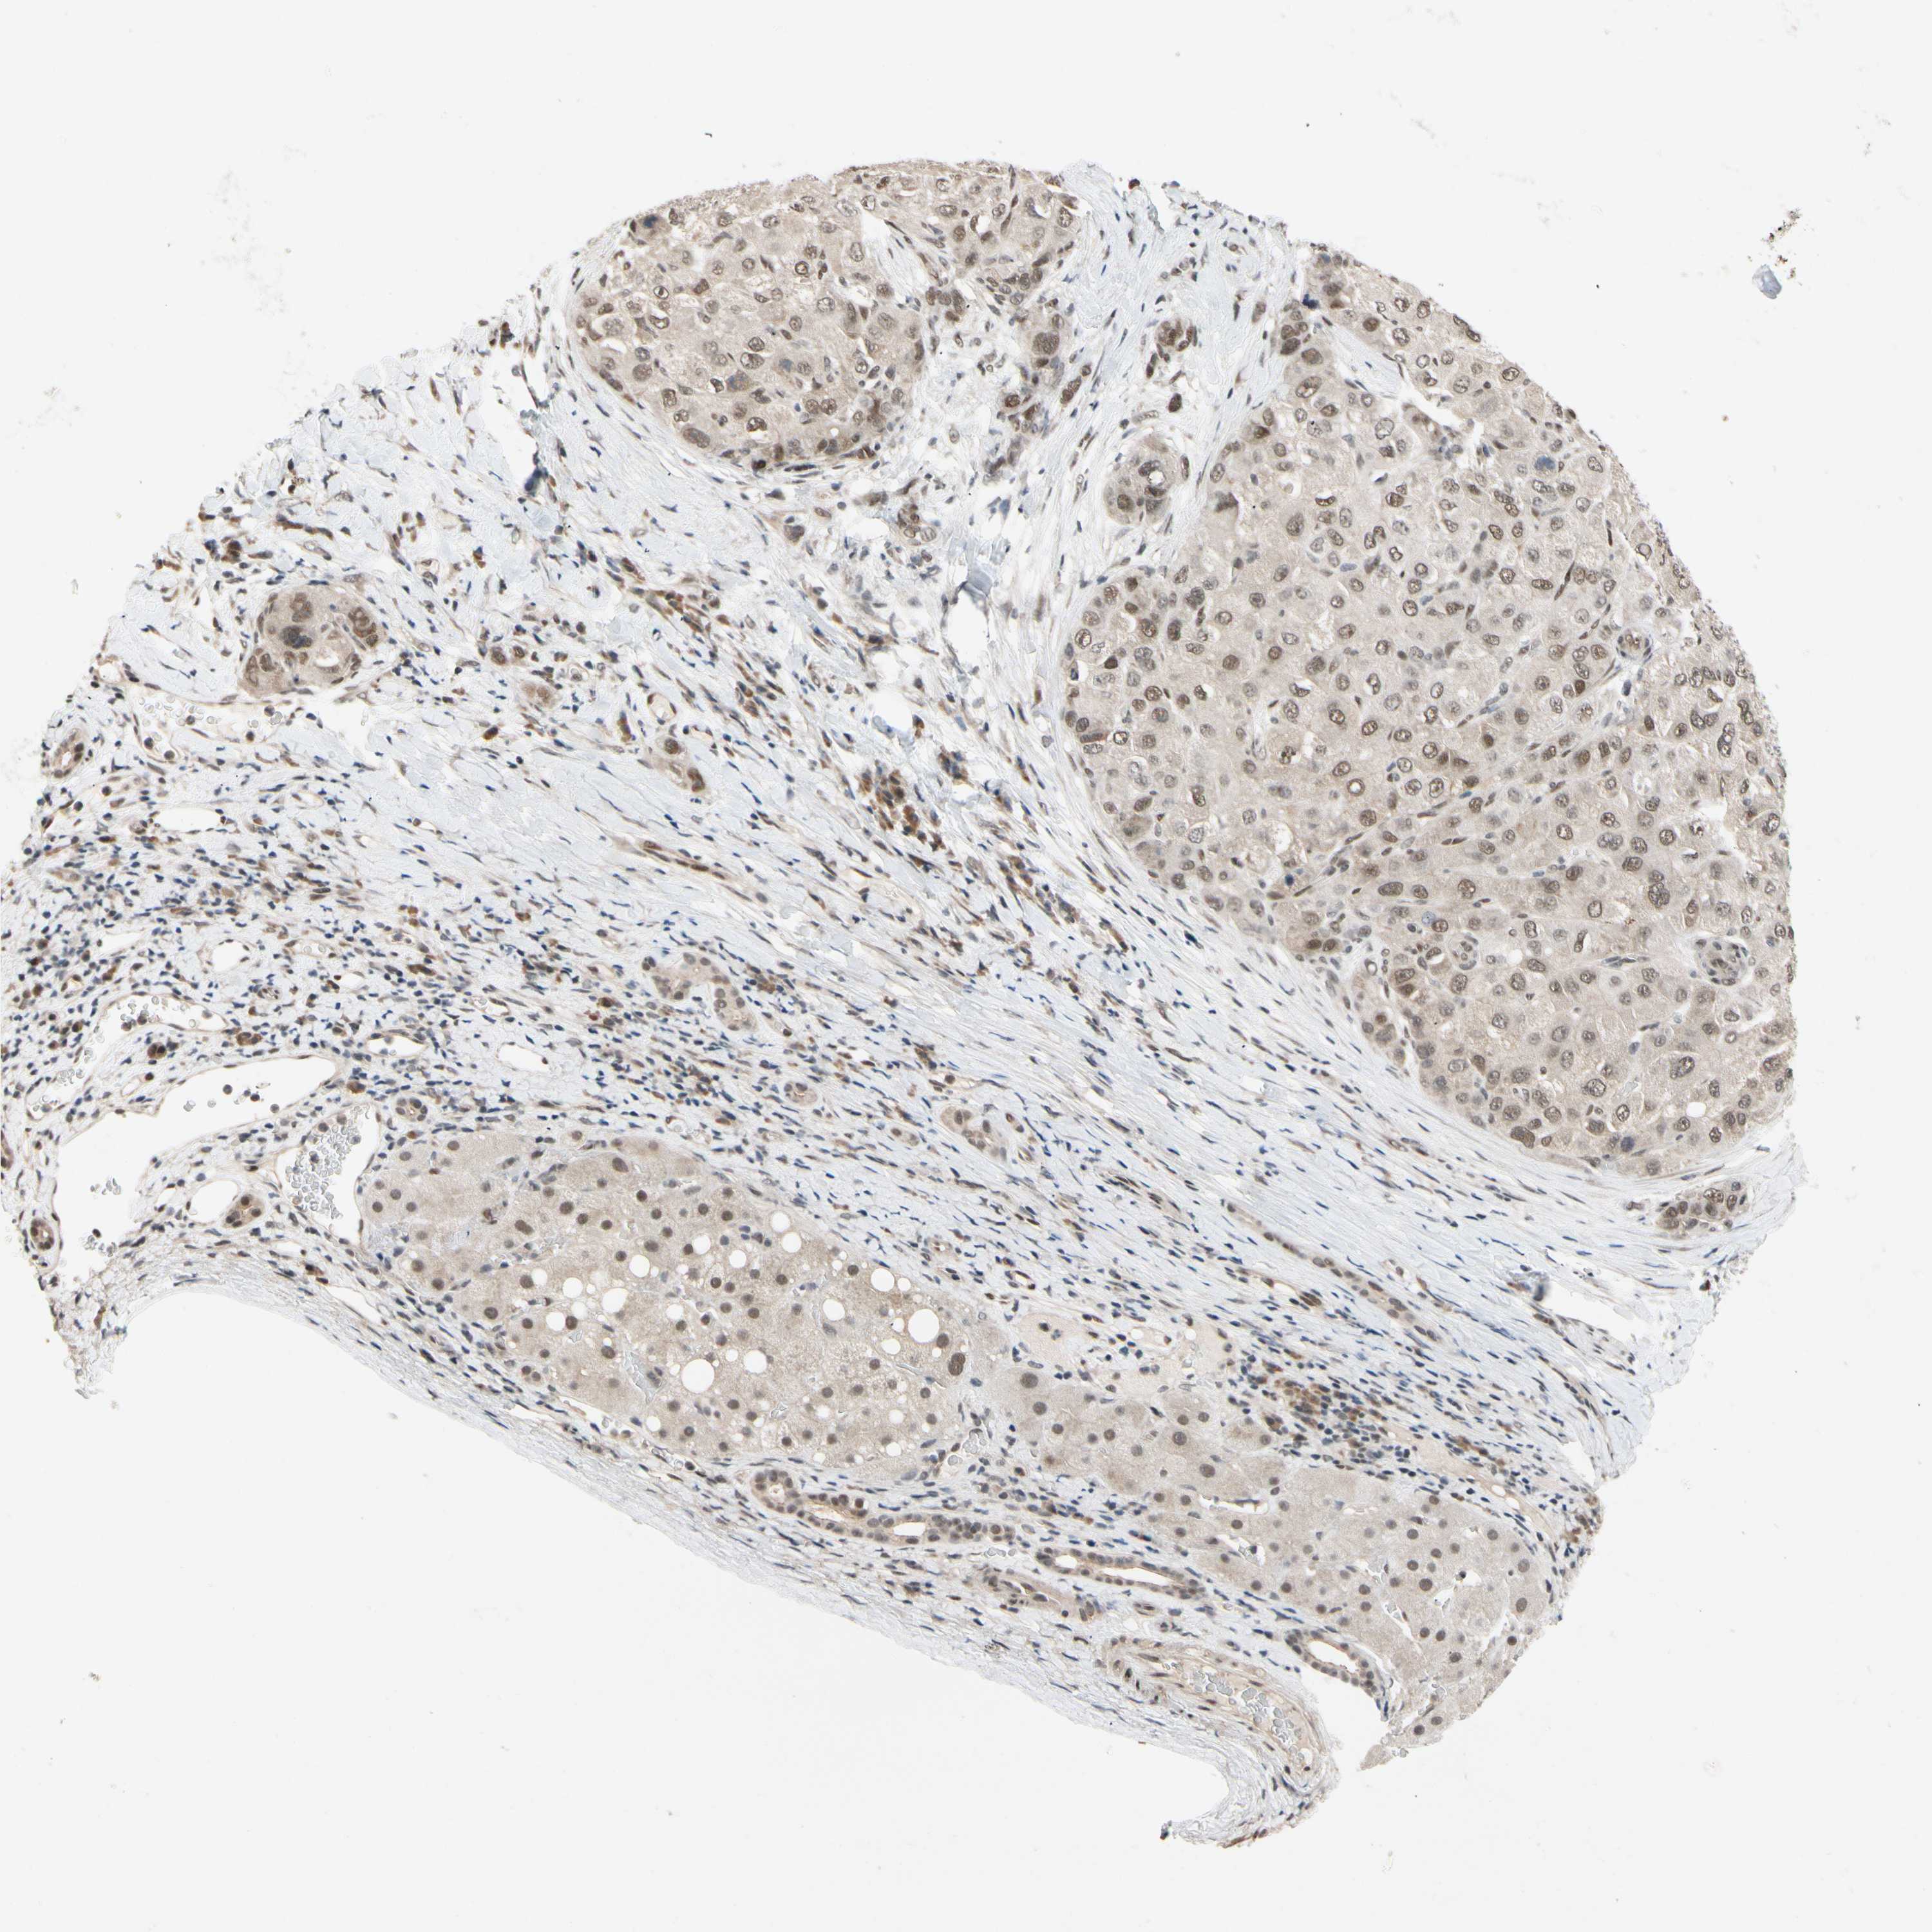

LIVER CANCER - Protein expressioni

A mouse-over function shows sample information and annotation data. Click on an image to view it in a full screen mode. Samples can be filtered based on level of antibody staining by selecting one or several of the following categories: high, medium, low and not detected. The assay and annotation is described here.

Note that samples used for immunohistochemistry by the Human Protein Atlas do not correspond to samples in the TCGA dataset.

Antibody stainingi

Antibody staining in the annotated cell types in the current human tissue is reported as not detected, low, medium, or high, based on conventional immunohistochemistry profiling in selected tissues. This score is based on the combination of the staining intensity and fraction of stained cells.

Each image is clickable and will lead to virtual microscopy that enables deeper exploration of all samples and also displays staining intensity scores, fraction scores and subcellular localization as well as patient and tissue information for each sample.

Antibody HPA008599

Antibody CAB031484

Staining

High

Medium

Low

Not detected

Intensity

Strong

Moderate

Weak

Negative

Quantity

>75%

75%-25%

<25%

None

Location

Nuclear

Cytoplasmic/membranous

Cytoplasmic/membranous,nuclear

Cholangiocarcinoma

Carcinoma, Hepatocellular, NOS